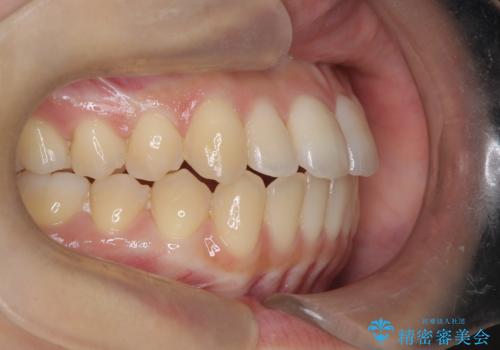

前歯のデコボコと突出を、目立たない矯正で解消

- 前歯のガタガタ(叢生)と、前歯が出ている(突出している)ことを気にされてご来院されました。精密な検査の結果、歯が並ぶスペースと、前歯を引っ込めるスペースの両方が不足していると診断。患者様のご希望に合わせ、透明で目立ちにくいインビザライン(マウスピース矯正)による治療計画を立案しました。スペースの確保は、奥歯全体を奥へ動かす遠心移動と、歯の側面をわずかに削る**IPR(歯間乳頭保護下ストリッピング)**を組み合わせて行い、前歯を効果的に引っ込めることを目指します。

今回の矯正治療では、透明なマウスピース型の装置インビザラインを使用しました。前歯を無理なく引っ込めるスペースを作るため、まず奥歯全体を後方へ移動させる遠心移動を実施。さらに、安全性が確保できる範囲で歯の側面をわずかに削るIPRを併用し、必要なスペースを確保しました。これらの処置により、前歯のデコボコが解消され、前に出ていた前歯も適切に引っ込みました。目立たない装置で治療を完結することで、叢生と突出感が解消され、機能性と審美性が向上した美しい口元を獲得していただけました。